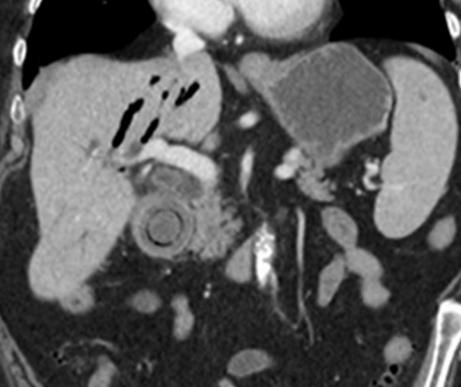

Bouveret 综合症

Bouveret 综合症 是由胆道系统结石通过胆肠瘘或经 Oddi 括约肌进入胃肠道引起的机械性消化道梗阻,常发生于老年女性中。 临床症状包括恶心呕吐、腹痛等。 CT 表现为肠管积液积气扩张,异位结石和胆道系统积气。

老年女性,腹痛、呕吐就诊。CT 平扫示胃腔扩张,十二指肠降部腔内见高密度结石。

老年女性,右上腹疼痛、呕吐。CT 增强示十二指肠球部结石,十二指肠球部及胆囊相通,存在瘘。